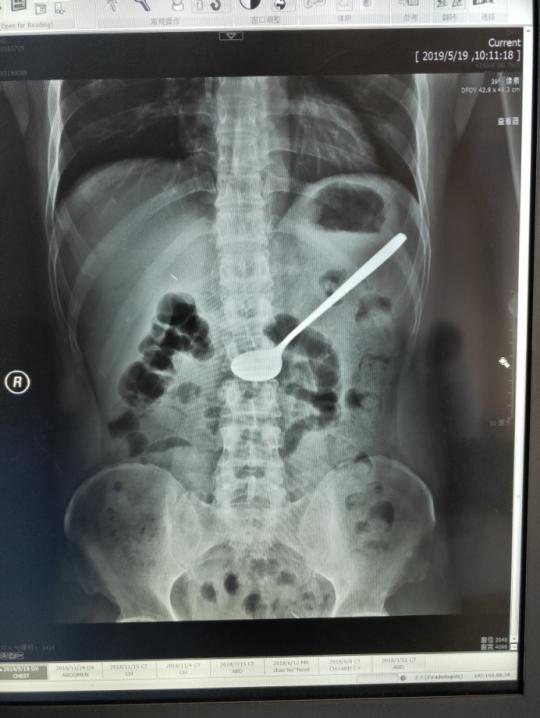

5月19日上午,像往常一样,消化内科主任李仁君在诊室忙碌的接诊。11时,诊室进来一位面容十分痛苦,捂着肚子满头大汗的患者,通过问诊,患者在5月18日下午误吞了一个长约20cm的铁质汤勺,曾求治过数家医院,均表示无法取出,并建议到上级医院进行外科手术治疗。于是,患者来到安医大附属巢湖医院胃肠外科就诊,经过X线检查未见消化道穿孔,见异物仍滞留于胃腔,考虑患者基础有尿毒症病史,如果进行胃部手术的话,对于患者来说术后创伤大,恢复期长,并发症多,并不是最佳治疗手段。遂请消化内科会诊评估能否内镜下处理。患者经过一天的转诊,已经身心疲惫,此时腹痛难忍。

李仁君主任接诊后,考虑患者吞服的为一个长约20cm的金属汤勺,表面光滑,无明显受力点,且重量大,普通的异物钳及网篮均无法有效取出。同时,患者又有尿毒症病史,长期进行着透析治疗,疾病决定了患者消化道管壁脆弱,操作不慎容易导致消化道粘膜损伤,严重者可以导致穿孔,尤其在通过贲门、食管中段及入口三处狭窄部时候更应注意。经过充分的综合考虑,与家属沟通征求同意后,李主任果断决定尝试通过内镜取出异物。